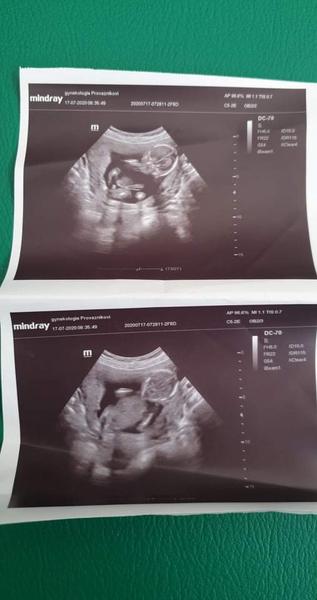

@ivuse20 ahoj muzes porovnat foku semnou mame mit možná chlapečka ale jistota to není